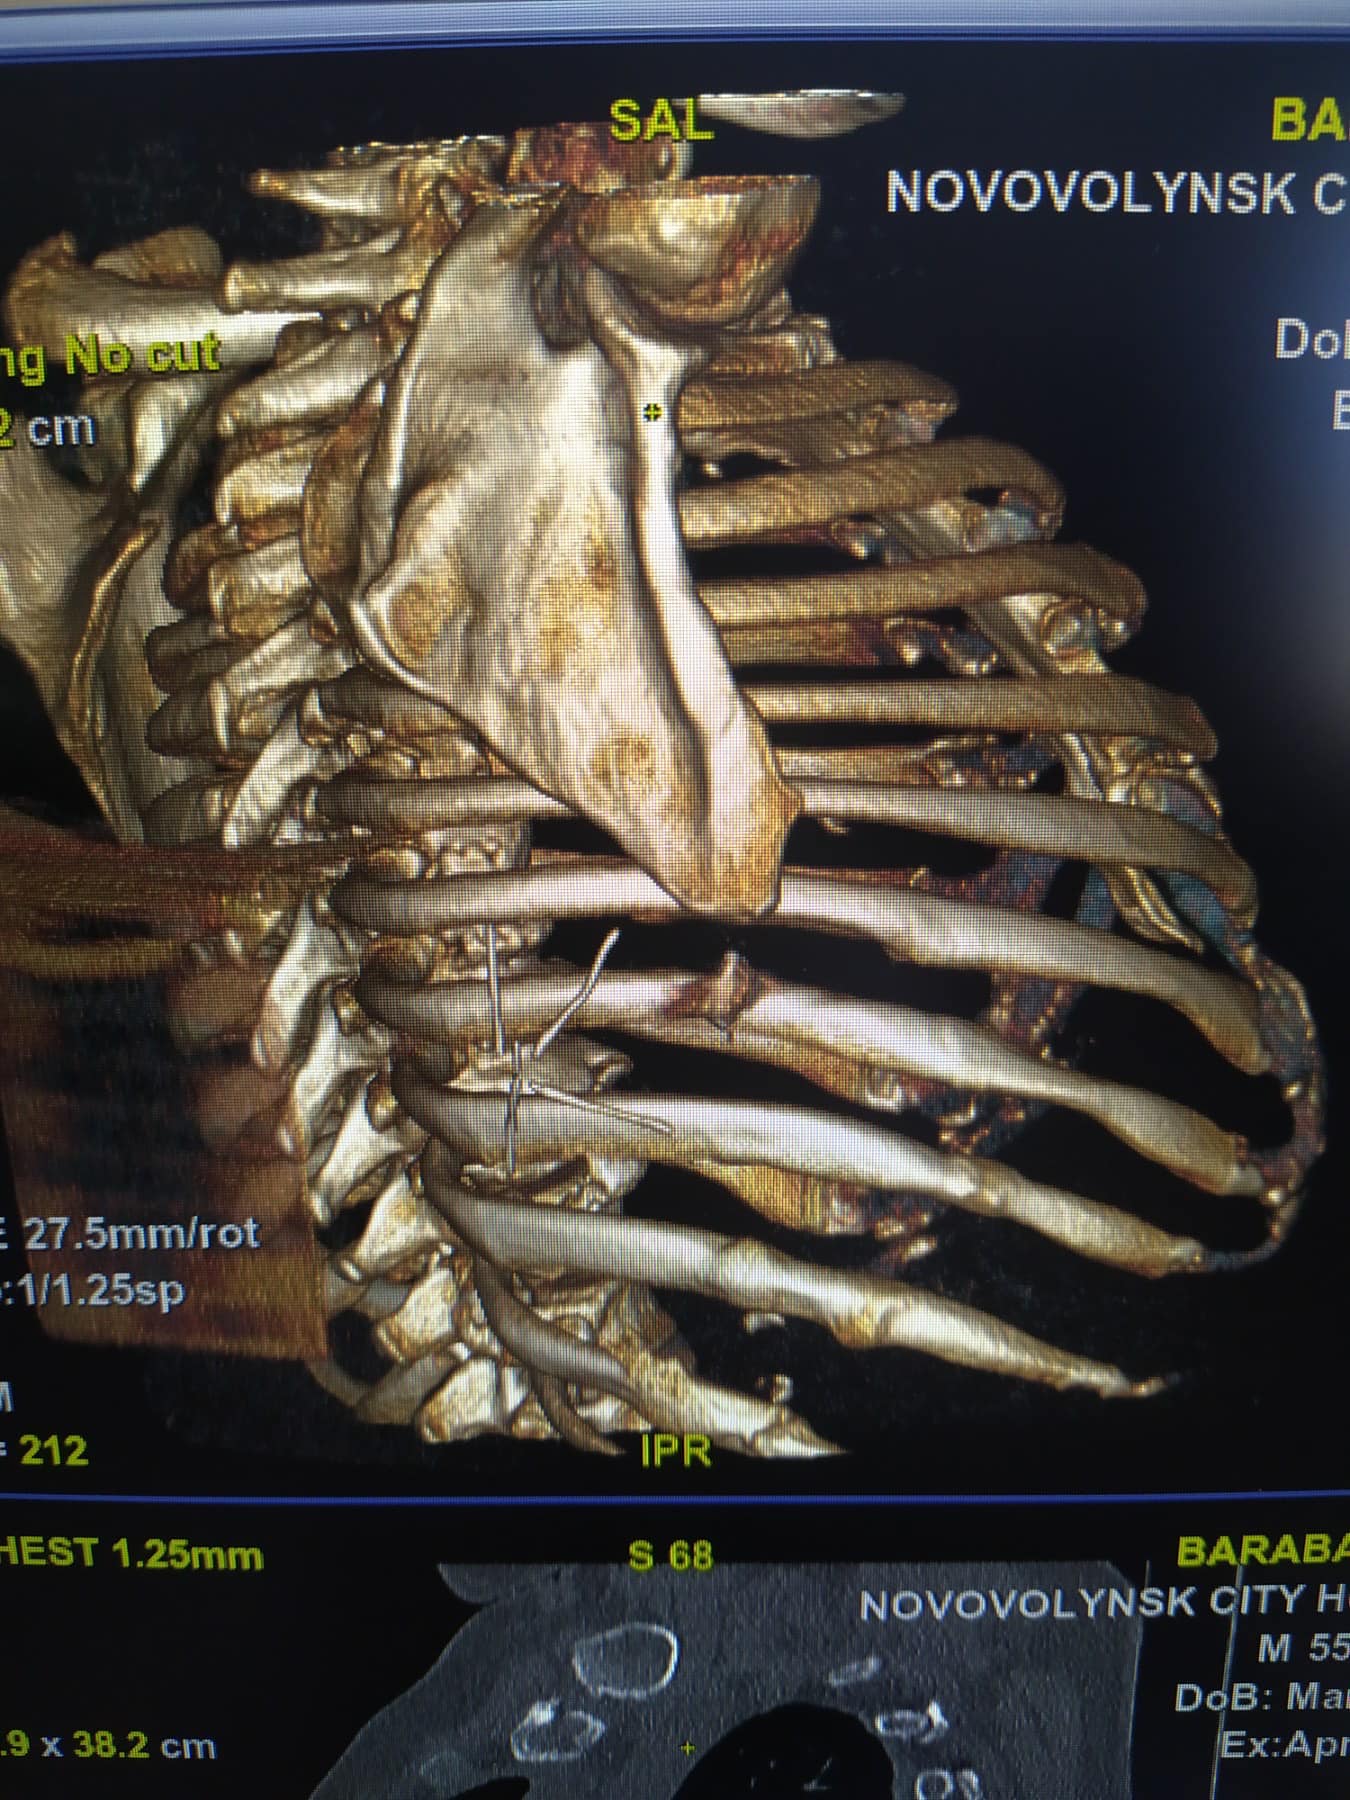

У КНП «НЦМЛ» звернувся пацієнт –

переселенець з Донецької області з приводу мінно-вибухового осколкового

поранення грудної клітки.

Сторонні тіла виявили під час КТ обстеження та провели

оперативне втручання.

З грудної стінки видалені металевий осколок (

2,0*1,0см) та шматки асфальту. Чоловіку пощастило, адже життєво важливі органи

не зачепило.